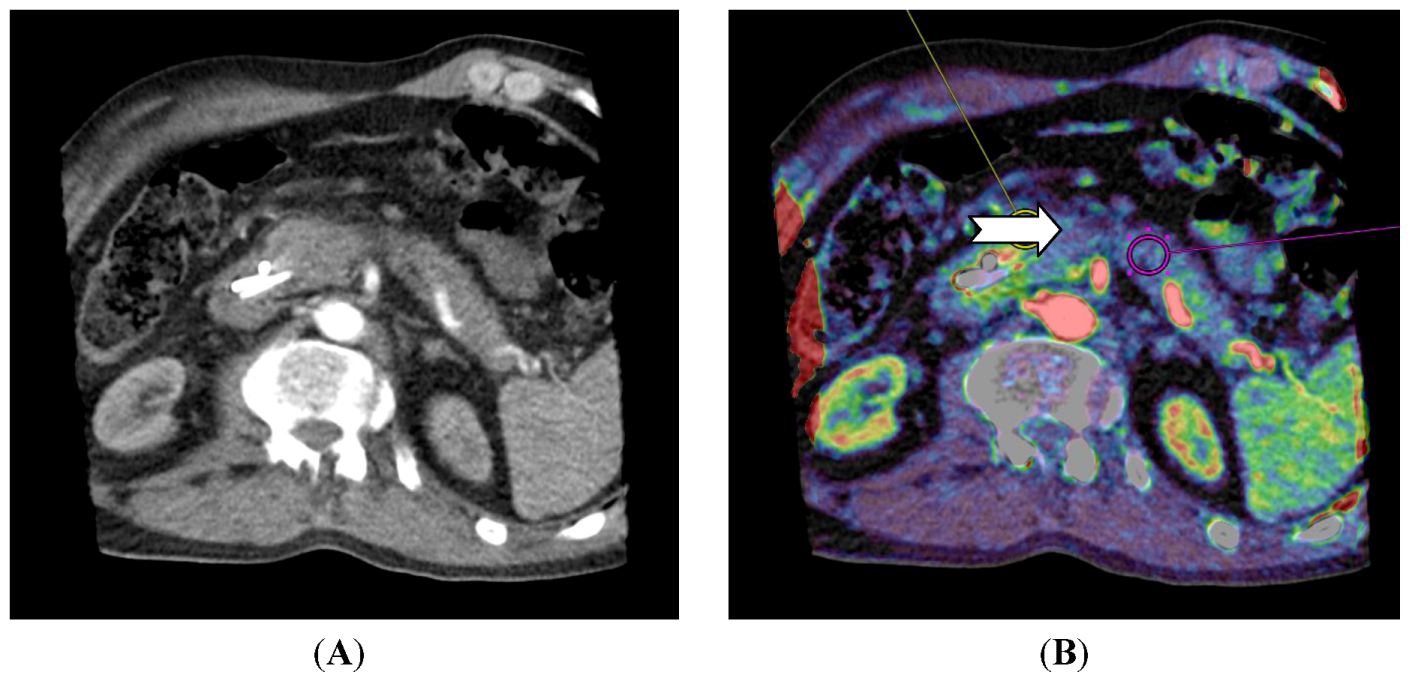

For pancreatic lesions, studies have shown that adenocarcinomas have a lower perfusion compared to normal pancreatic tissue [42,43]. For neuroendocrine tumors in the pancreas, D’ Assignies et al. [33] showed a higher perfusion and a positive correlation between blood flow and MVD (Figure 4).

Figure 4.

CT perfusion examination of a 63-year-old male with a pancreatic mass. The tumor has a neuroendocrine component and CT perfusion shows higher blood flow (110.2 mL/min/100 mL) (arrow) compared to the normal pancreatic tissue (83.7 mL/min/100 mL) (B). The patient has stents in the common bile duct (A) which causes image and perfusion artifacts in the pancreatic head. (Images reconstructed with Vitrea 6.2, Vital Images A Toshiba Medical Systems Group).